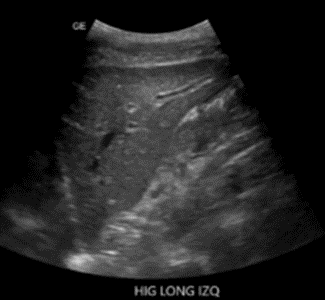

Hígado con aumento de la ecogenicidad de la triada portal (cielo estrellado).

Hígado: conserva forma, tamaño y contornos regulares. El parénquima se visualiza ecográficamente heterogéneo, con aumento a nivel de la triada portal en cielo estrellado, sin áreas de focalización intraparenquimatosa. El sistema biliar intrahepático luce normal